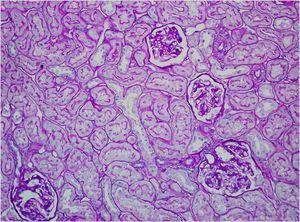

La biopsia renal del varón mostró ocho glomérulos: tres de ellos estaban esclerosados, dos presentaban lesiones de esclerosis segmentaria y focal con hialinosis y sinequia capsular (figura 1), otros dos marcada fibrosis capsular con ligera retracción del ovillo, y el restante un ligero incremento de la celularidad mesangial. El intersticio reveló atrofia tubular, fibrosis e infiltrado inflamatorio crónico. En las arteriolas se observó una intensa hialinosis subendotelial con marcada reducción luminal. La inmunofluorescencia mostró mínimo depósito inespecífico de IgM; y la ultraestructura, megamitocondrias con marcada distorsión de las crestas y aumento de la osmiofilia de la matriz interna a nivel podocitario (figura 2). En el segundo caso, inicialmente se obtuvo un único glomérulo para microscopía óptica sin hallazgos relevantes, salvo una mínima esclerosis arteriolar. Se realizó una nueva biopsia cinco años después en la que se obtuvo un cilindro con ocho glomérulos ópticamente normales (figura 3). En la microscopía electrónica destacaba, igual que en el primer caso, la presencia de mitocondrias de gran tamaño con distorsión de las crestas y con una matriz interna desestructurada en los podocitos, con ausencia de laminación de la membrana basal glomerular, así como focos con adelgazamiento de esta, observándose de forma focal zonas con desaparición de pedicelos (figuras 4 y 5), no obstante, y debido a la heteroplasmia, también es posible ver mitocondrias de aspecto normal (figura 6)

Figura 1. Glomeruloesclerosis focal y segmentaria.

Figura 3. PAS (20x). Dos glomérulos de aspecto normal. Mínima esclerosis arteriolar.